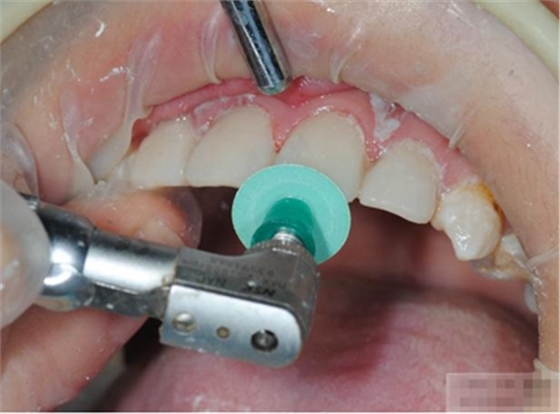

釉質(zhì)邊緣要用橡皮輪拋光

拋光可以去除懸釉。這樣經(jīng)過(guò)車針打磨過(guò)的釉質(zhì)表面會(huì)更加均一,形成良好的邊緣封閉。